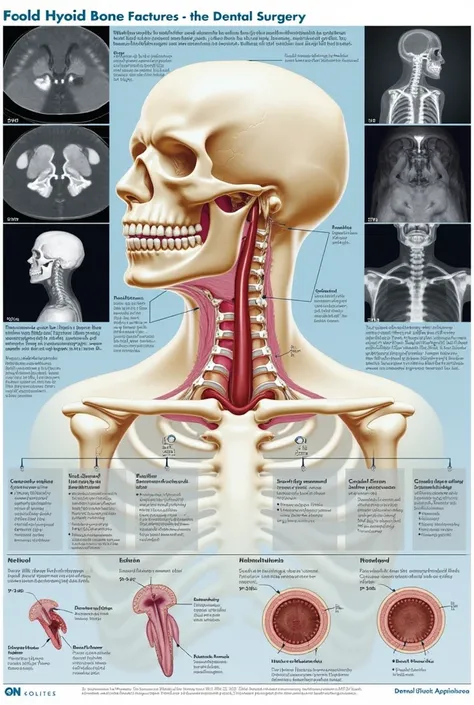

Checkpoint & LoRA

Checkpoint

SeaArt Infinity

#SeaArt Infinity